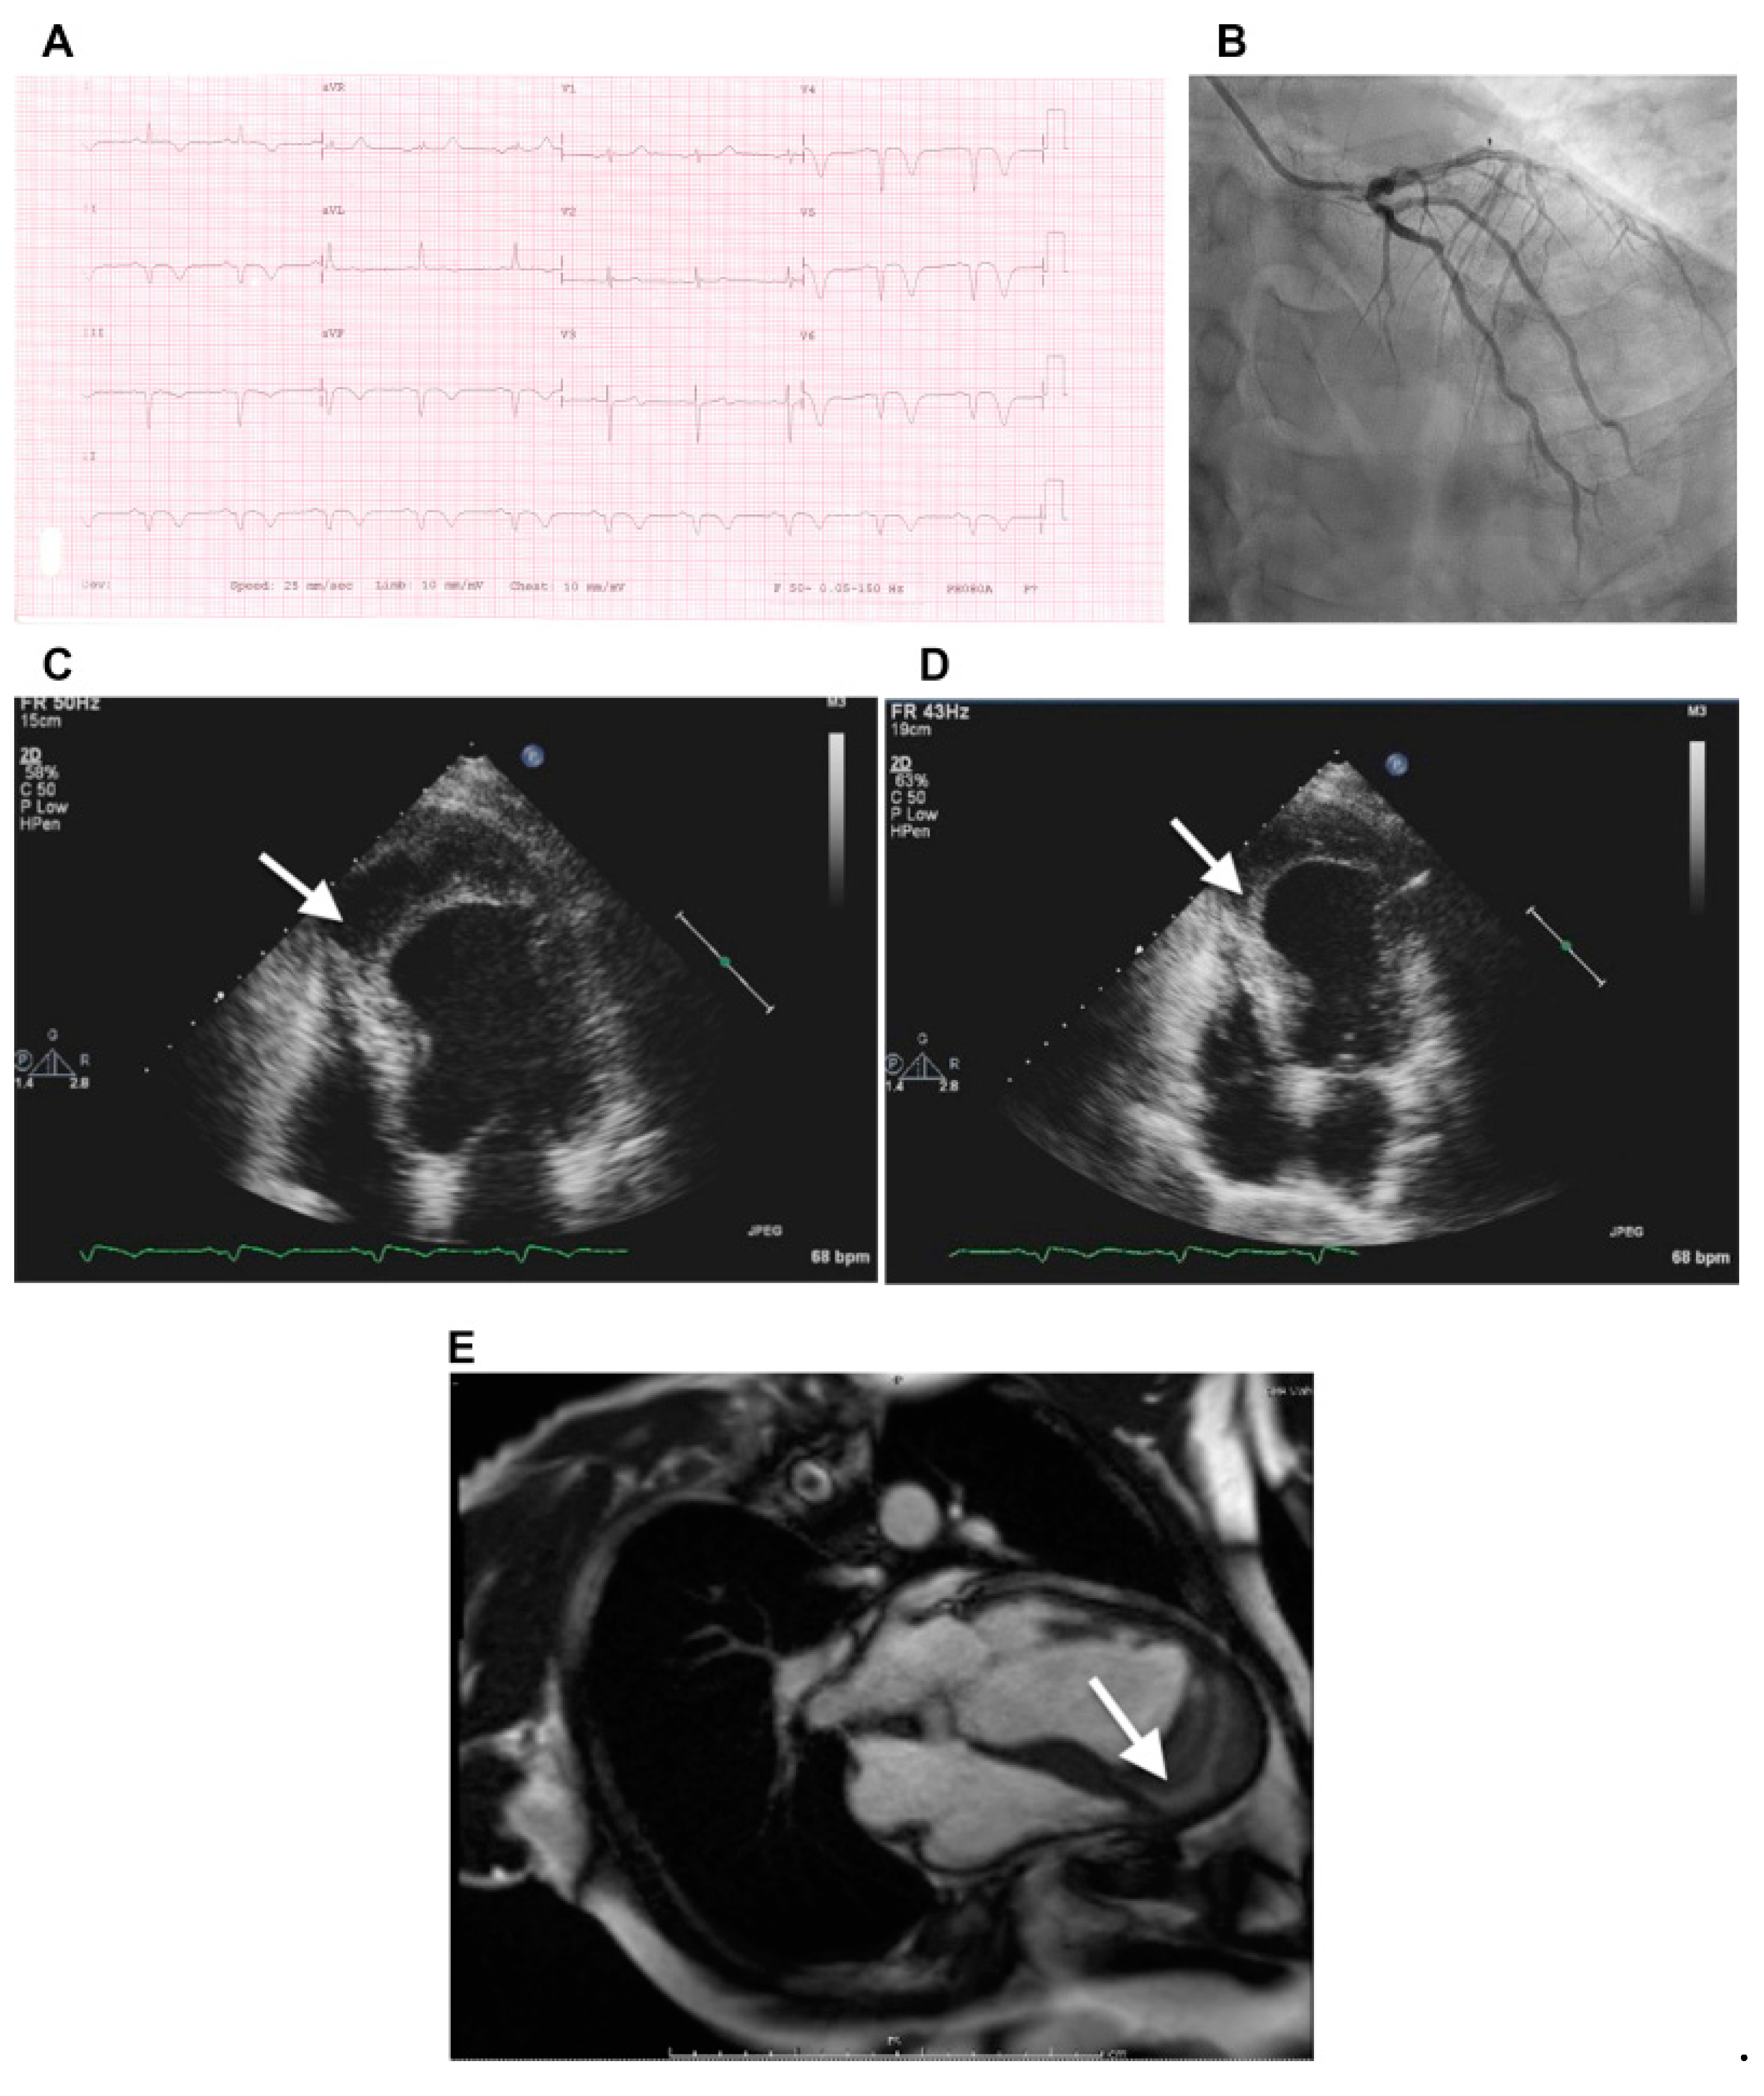

Less common pathologies affecting the IVS include aneurysm [66], diverticulum [67], and lipomatous hypertrophy [68]. Intramyocardial dissecting hematoma is a rare form of cardiac rupture that may occur following MI, chest trauma, or percutaneous intervention. It can develop in the LV free wall, RV, or IVS, and consists of blood infiltration into and through the myocardial wall (Figure 3) [69].

Figure 3.

(A) Electrocardiogram at presentation shows biphasic T wave in lead V3, deep T-wave inversion in leads V4, V5, and V6, and Q waves with T-wave inversion in the inferior leads, consistent with angiographic findings. (B) Coronary angiogram shows moderate stenosis at the proximal segment of the left anterior descending coronary artery, severe stenosis at midsegment, and complete total occlusion in the distal segment. (C–E) Transthoracic two-dimensional echocardiographic and cardiac magnetic resonance views of IDH. (C,D) At presentation, apical four-chamber view showing dissecting echo-free cavity (arrow). (E) An IDH was confirmed by gadolinium-enhanced magnetic resonance imaging, revealing a large thrombus (arrow) within the apical intramyocardial dissection cavity containing the hematoma in the apical segment. Roslan A, et al. CASE (Phila). 2017 August; 1(4): 159–162 [69].